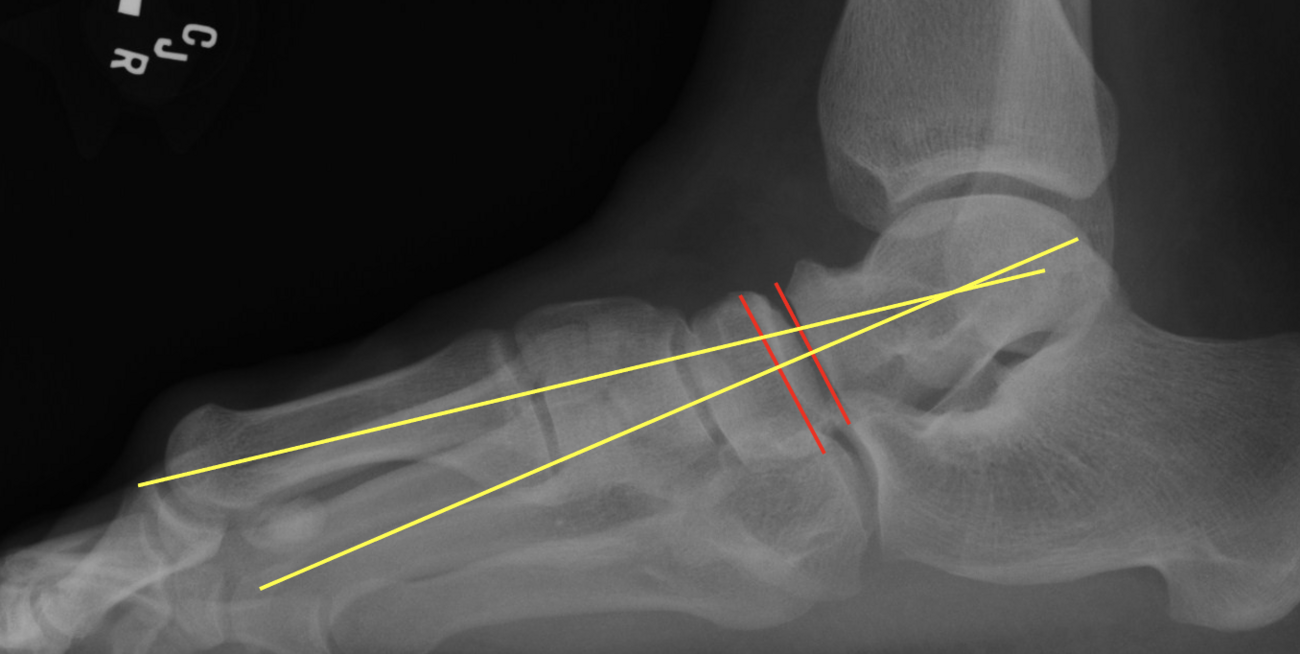

As the Ponseti grew in popularity, I noted significant discrediting of surgical options. Well long-term studies on the Ponsetti are starting to surface, and it is not without its own problems. Kids are lost to follow-up, not braced appropriately, and just like we saw in long-term studies with the posteromedial release, there is a lot of undercorrection. Casting cannot and will not ever achieve what the Cincinnati release can. Although the Ponseti may not have the complications of the Cincinnati, X-ray data reveals that the Ponseti cannot and does not correct everything, most critically, talocalcaneal angles. You can not solve a clubfoot with an Achilles tenotomy and an overly aggressive casting. As these kids develop, I see residual met adductus and calcaneal varus, along with casting complications like flat top talus and met primus elevatus. I then see that they will develop DJD just like posteriomedial and Cincinnati releases. Haasbeck and team in 1997 reported that the Cincinnatti required fewer procedures than the posteromedial release over the life of their study.14 Thomas performed a systematic review in 2019, concluding that the longer the study follow-up, the greater the relapse rate and the poorer the results of the Ponseti.15 For most of us who have done clubfeet surgery for many years, this is no surprise. Among the 46 studies meeting inclusion criteria, they saw as high as 67 percent required future surgeries to address relapse.15

One of the most disturbing complications with any casting is the development of flat top talus. Overly aggressive attempts to dorsiflex the ankle often lead to met primus elevatus, but the flat top talus ruins the ankle joint during development. When I work with residents and students, I always stress the importance of avoiding dorsiflexion completely during the casting phase simply because I do not want to create a deformation of the talus. I reserve all of my sagittal plane correction for the Achilles lengthening and posterior capsule release. Unfortunately, I see more and more cases of flat top talus as a result of the Ponseti method. Khan and colleagues in 2021 reported a significant increase in their study and review of the literature, blaming it solely on overly aggressive casting and manipulation.16

So, to summarize, true congenital clubfeet have abnormal talar bodies, which lead to abnormal ankle and subtalar joints with short Achilles and tight posterior tibial tendons. Regardless of treatment, there is nothing anyone can do to make the talus a normal bone. Many of these cases can and will develop additional deformities. Only the Cincinnati release can address every issue associated with the deformity, but it is NOT a cure. The Ponseti procedure is a total compromise, also NOT a cure. The sooner everyone treats the Ponseti as a compromise, I believe we will be far happier with the outcomes. I remember discussing this with others treating pediatric orthopedic issues during the rise of the Ponseti in the early 2000s. We all agreed, undercorrecting the deformity will lead to more surgeries and residual deformities. Until we all face the reality that clubfeet are a genetic deformity and not just a positional deformity, we will never make them perfect. Thus, athletes and the military will put any and all clubfeet patients to the test. There is no doubt that exceptions exist, but in time, at least based on our limited review of over 1000 clubfeet and 250 cases we saw in the military, no one is immune to complications, arthritis, and ultimately disability.

Here is a typical case presentation. A 21-year-old Marine at Ft. Leonard Wood for training underwent a Cincinnati release at one year old and had stellar follow-up. Her surgeon even wrote her medical waiver for entrance into the Marines. She ran track in high school. She finished boot camp and completed all of her Marine training, but now has chronic pain. She no longer can run. She hasn’t passed her physical training in over a year. She developed talonavicular DJD. By all accounts, her overall clubfoot should be rated an A+; no residual deformity, normal talocalcaneal angles on AP and lateral views, no equinus, no residual varus, only slight met primus elevatus, but no signs of a flattop talus. Clinically, she lacks subtalar range of motion, which I commonly find post-clubfoot release of any kind. So many in the military do very well for a while, but the demands of the military eventually catch up to them. We all root for clubfeet to make it, but the odds are stacked against them.